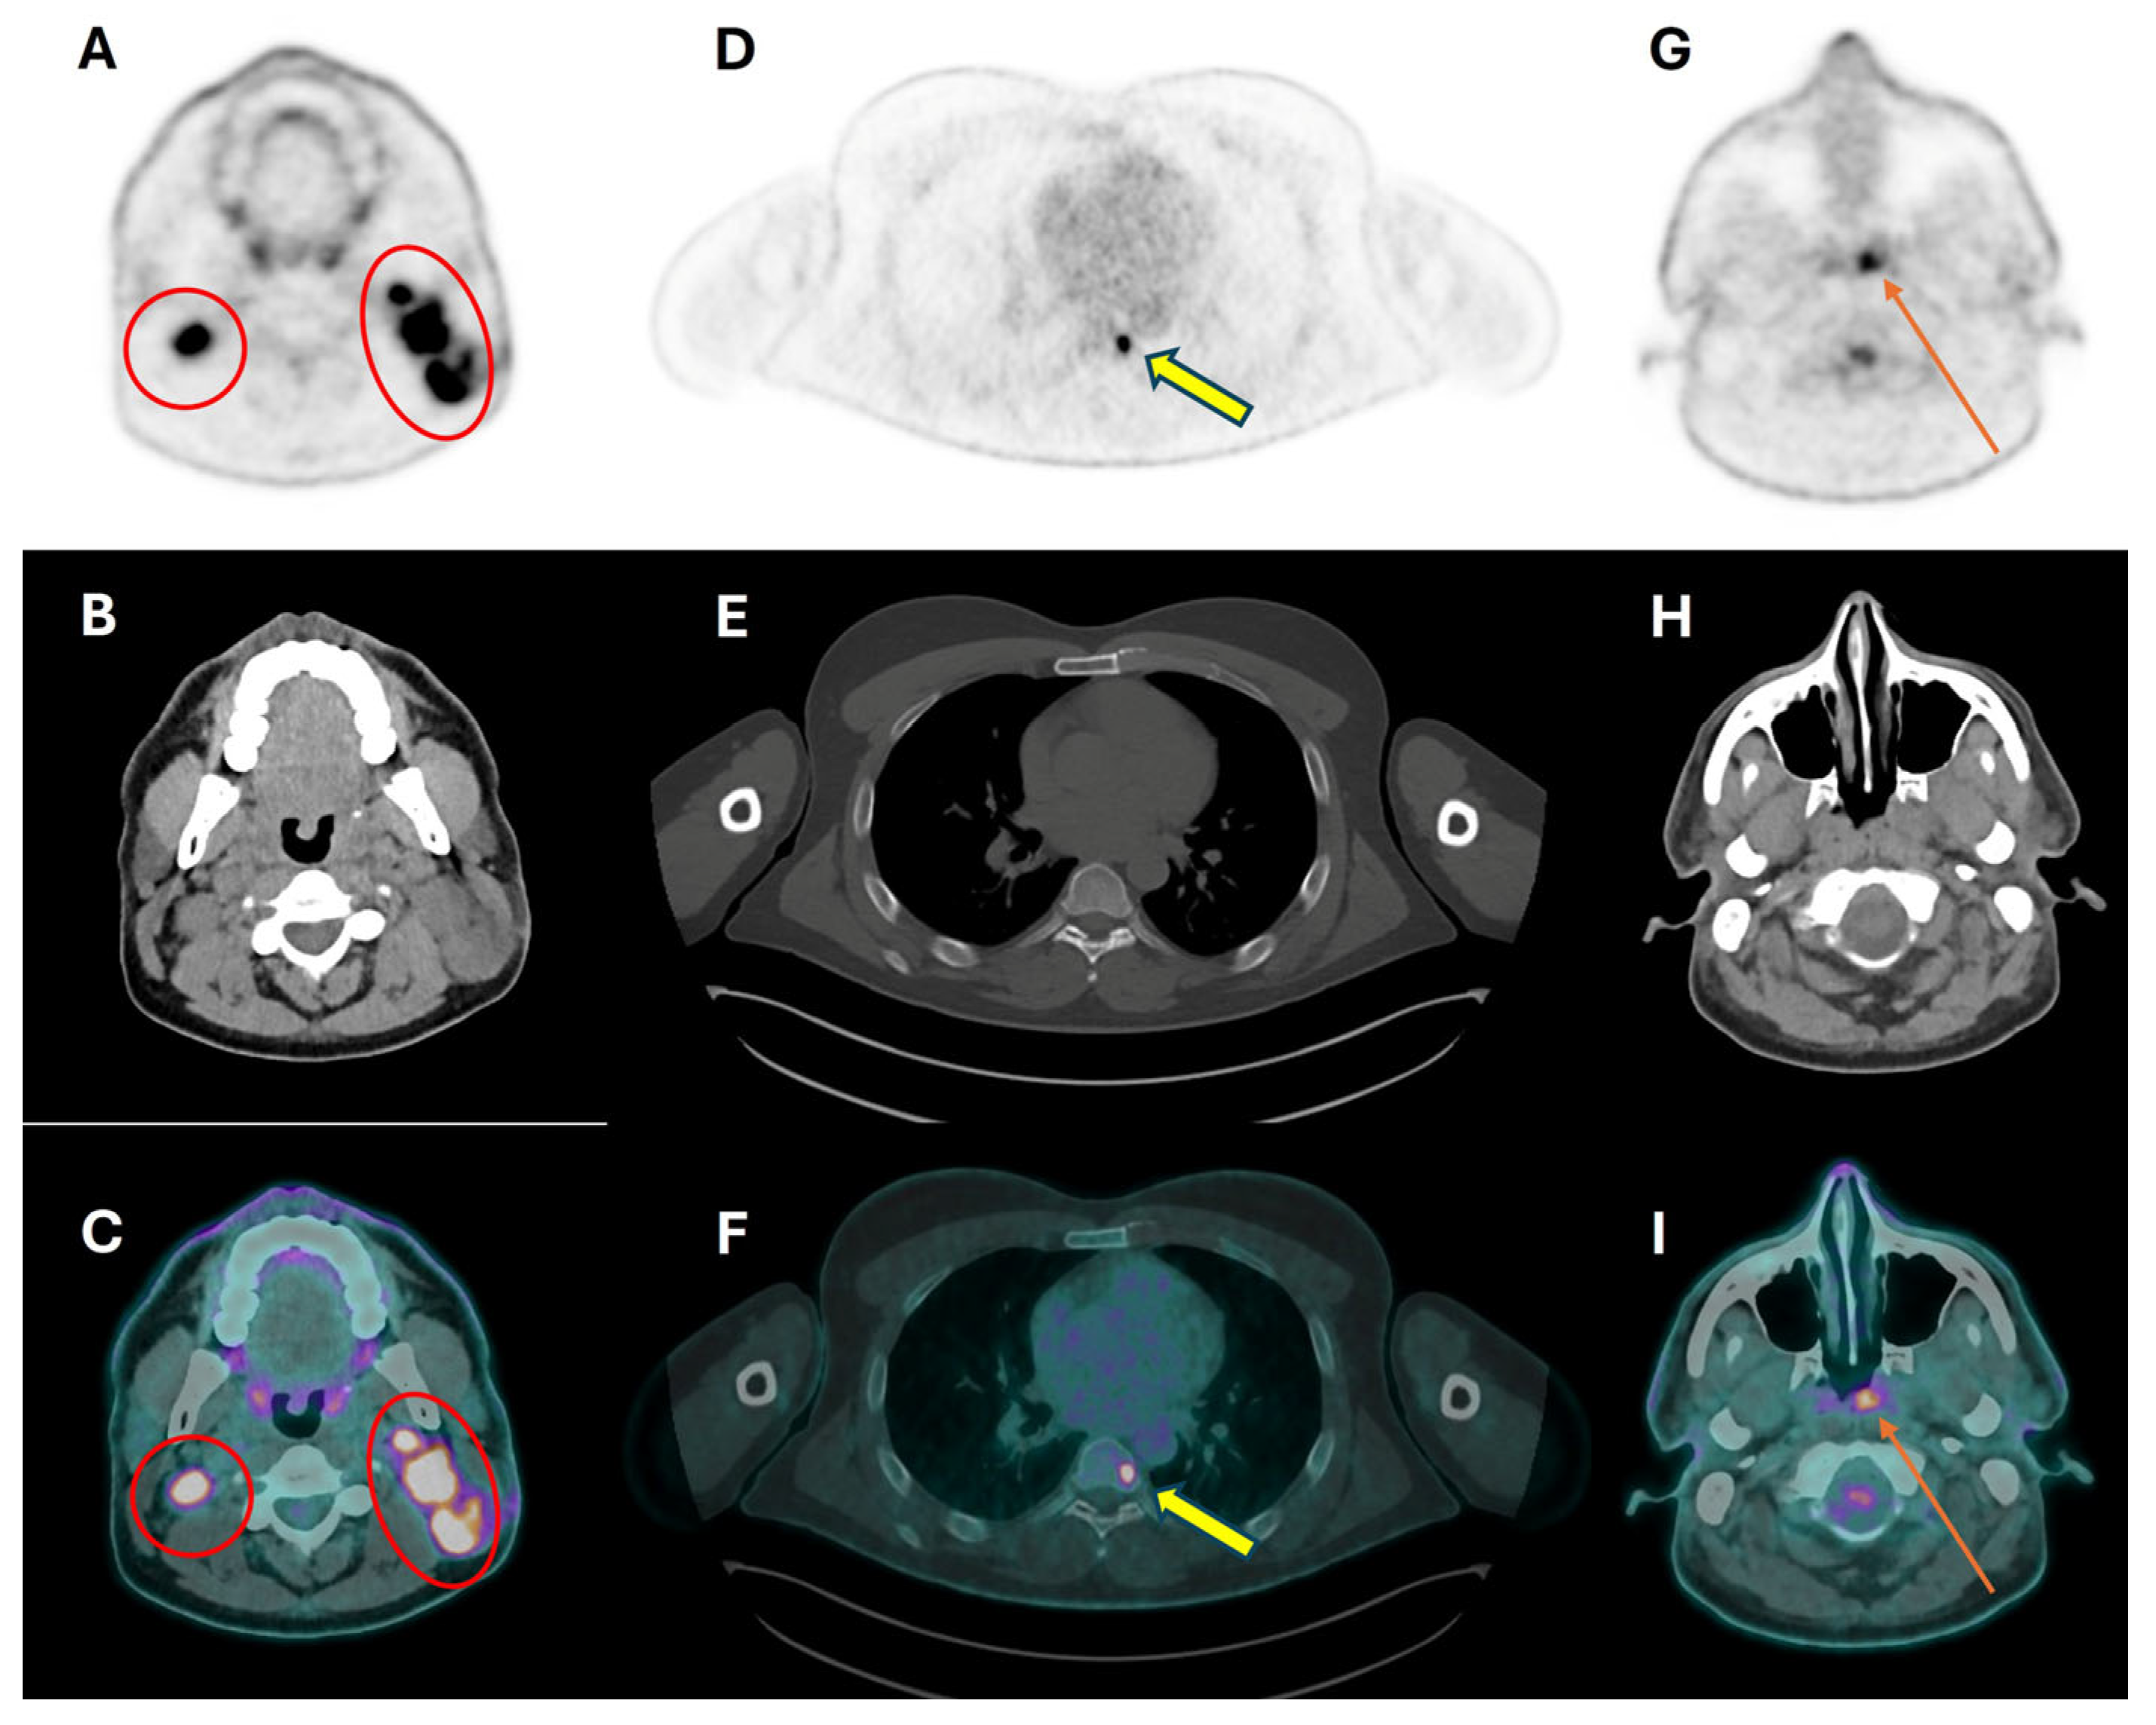

3.2. Cervical Lymph Node Assessment

3.3. Distant Metastasis Assessment

3.4. Second Primary Tumor Assessment

- Haerle, S.K.; Strobel, K.; Ahmad, N.; Soltermann, A.; Schmid, D.T.; Stoeckli, S.J. Contrast-enhanced 18F-FDG-PET/CT for the assessment of necrotic lymph node metastases. Head Neck 2011, 33, 324–329. [Google Scholar] [CrossRef] [PubMed]